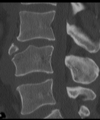

Fratura compressiva da coluna lombar

Causa achatamento do corpo e acunhamento geralmente anterior.

Tipo mais comum de fratura da coluna lombar

Estável.

Mecanismo flexão anterior ou lateral